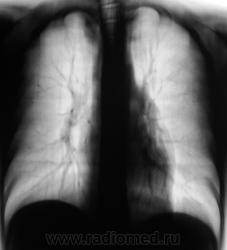

Пациента прислали "из туба" для томографии верхушек.

Получили такие картинки. Ваше мнение уважаемые коллеги?

Процесс не в легком, это деформация заднего отрезка 2 ребра справа или мне кажется ?

Спасибо за высказанное мнение коллега. Мы, также расценили, как деформацию и некоторую "гипертрофию" заднего фрагмента 2 ребра.